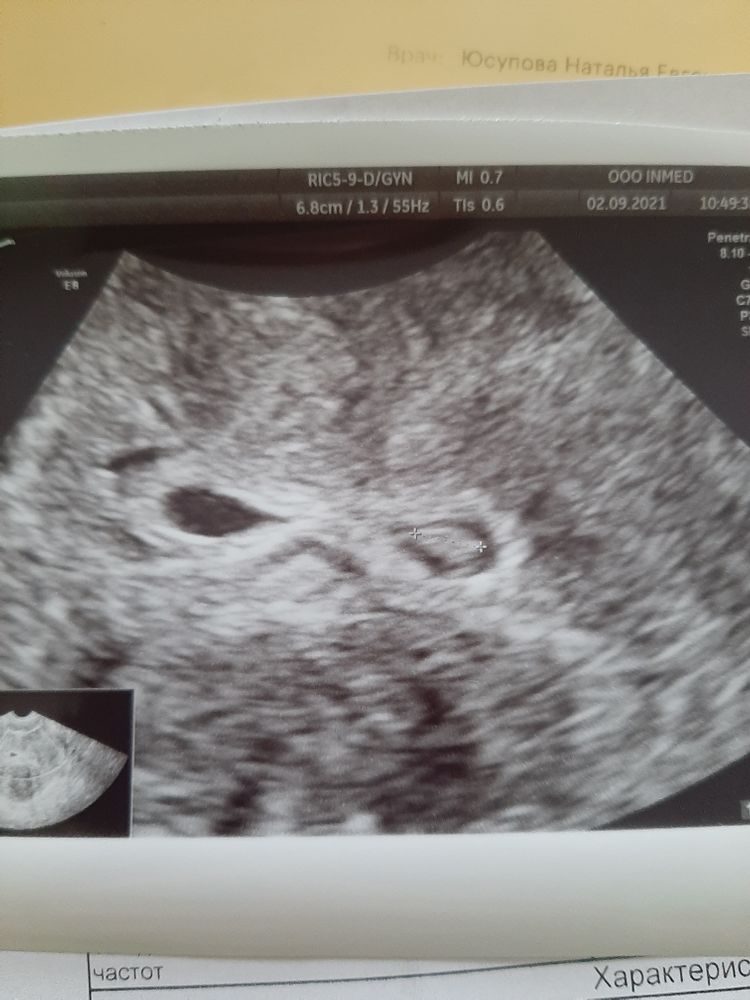

Девочки подскажите, может у кого то так было....Пя в виде цифры 8 ,эмбрион 6мм и сердцебиение....но из за миом пя вытянутое...пя 30 на 7 мм.миома из стенки давит на пя,но в полости нет миом